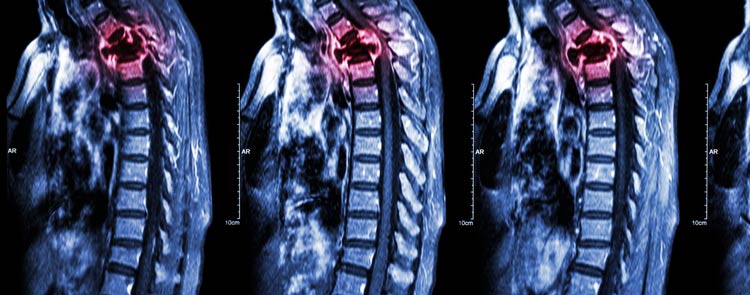

Фото 1. Разрушение метастазой костной ткани

Фото 2. Вид тазовых костей на рентгене

Более доступный и бесконтактный метод это рентген. Однако он выявляет лишь зрелую вторичную метастазу, когда разрушению уже подвергся значительный объем кости. Преимущество рентгенологии заключается возможности дифференцирования вторичного новообразования, исходя из его типа. Разная окраска пятен на фото, будет говорить о различной их природе.

Более доступный и бесконтактный метод это рентген . Однако он выявляет лишь зрелую вторичную метастазу, когда разрушению уже подвергся значительный объем кости. Преимущество рентгенологии заключается возможности дифференцирования вторичного новообразования, исходя из его типа. Разная окраска пятен на фото, будет говорить о различной их природе.